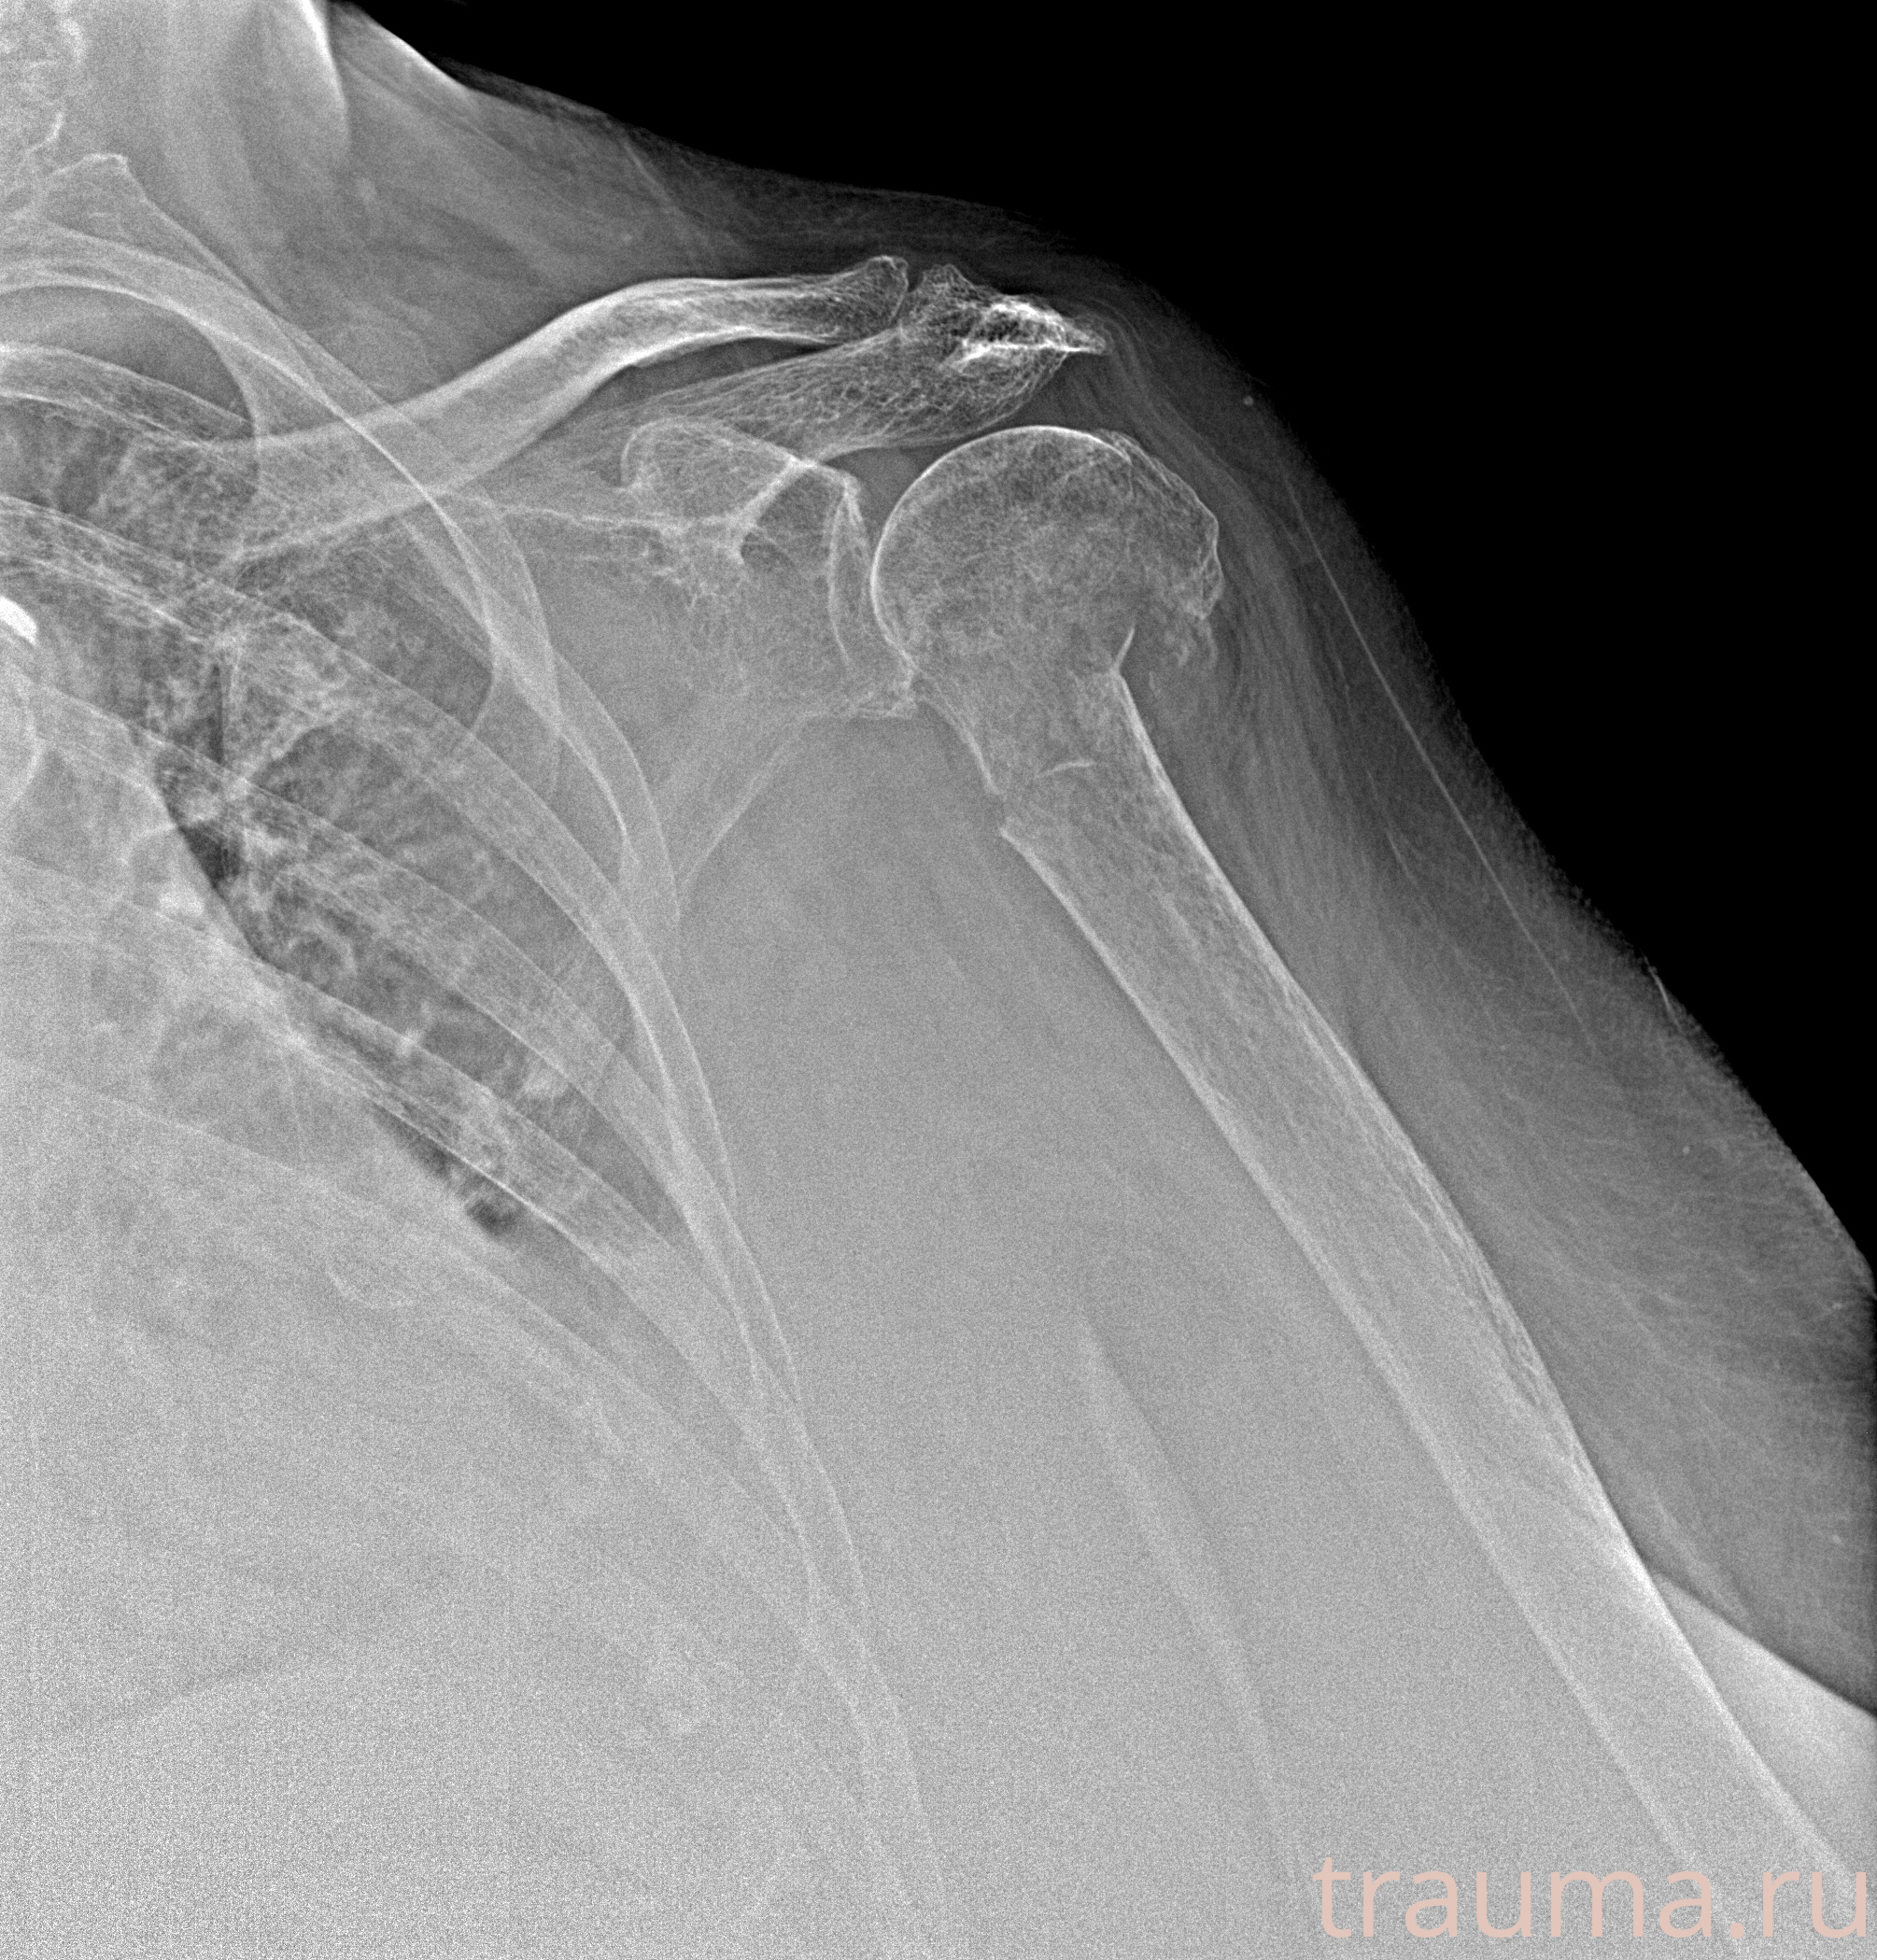

Рентгенограммы

Рентген на дому: по вашему адресу приезжает врач-рентгенолог, травматолог-ортопед с мобильным рентгеновским аппаратом, проводит диагностику травмы или заболевания, делает необходимые рентгенограммы, дает рекомендации по дальнейшему лечению. Получить качественные снимки в домашних условиях возможно благодаря уникальной методике, разработанной МосРентген Центром для института  Склифосовского